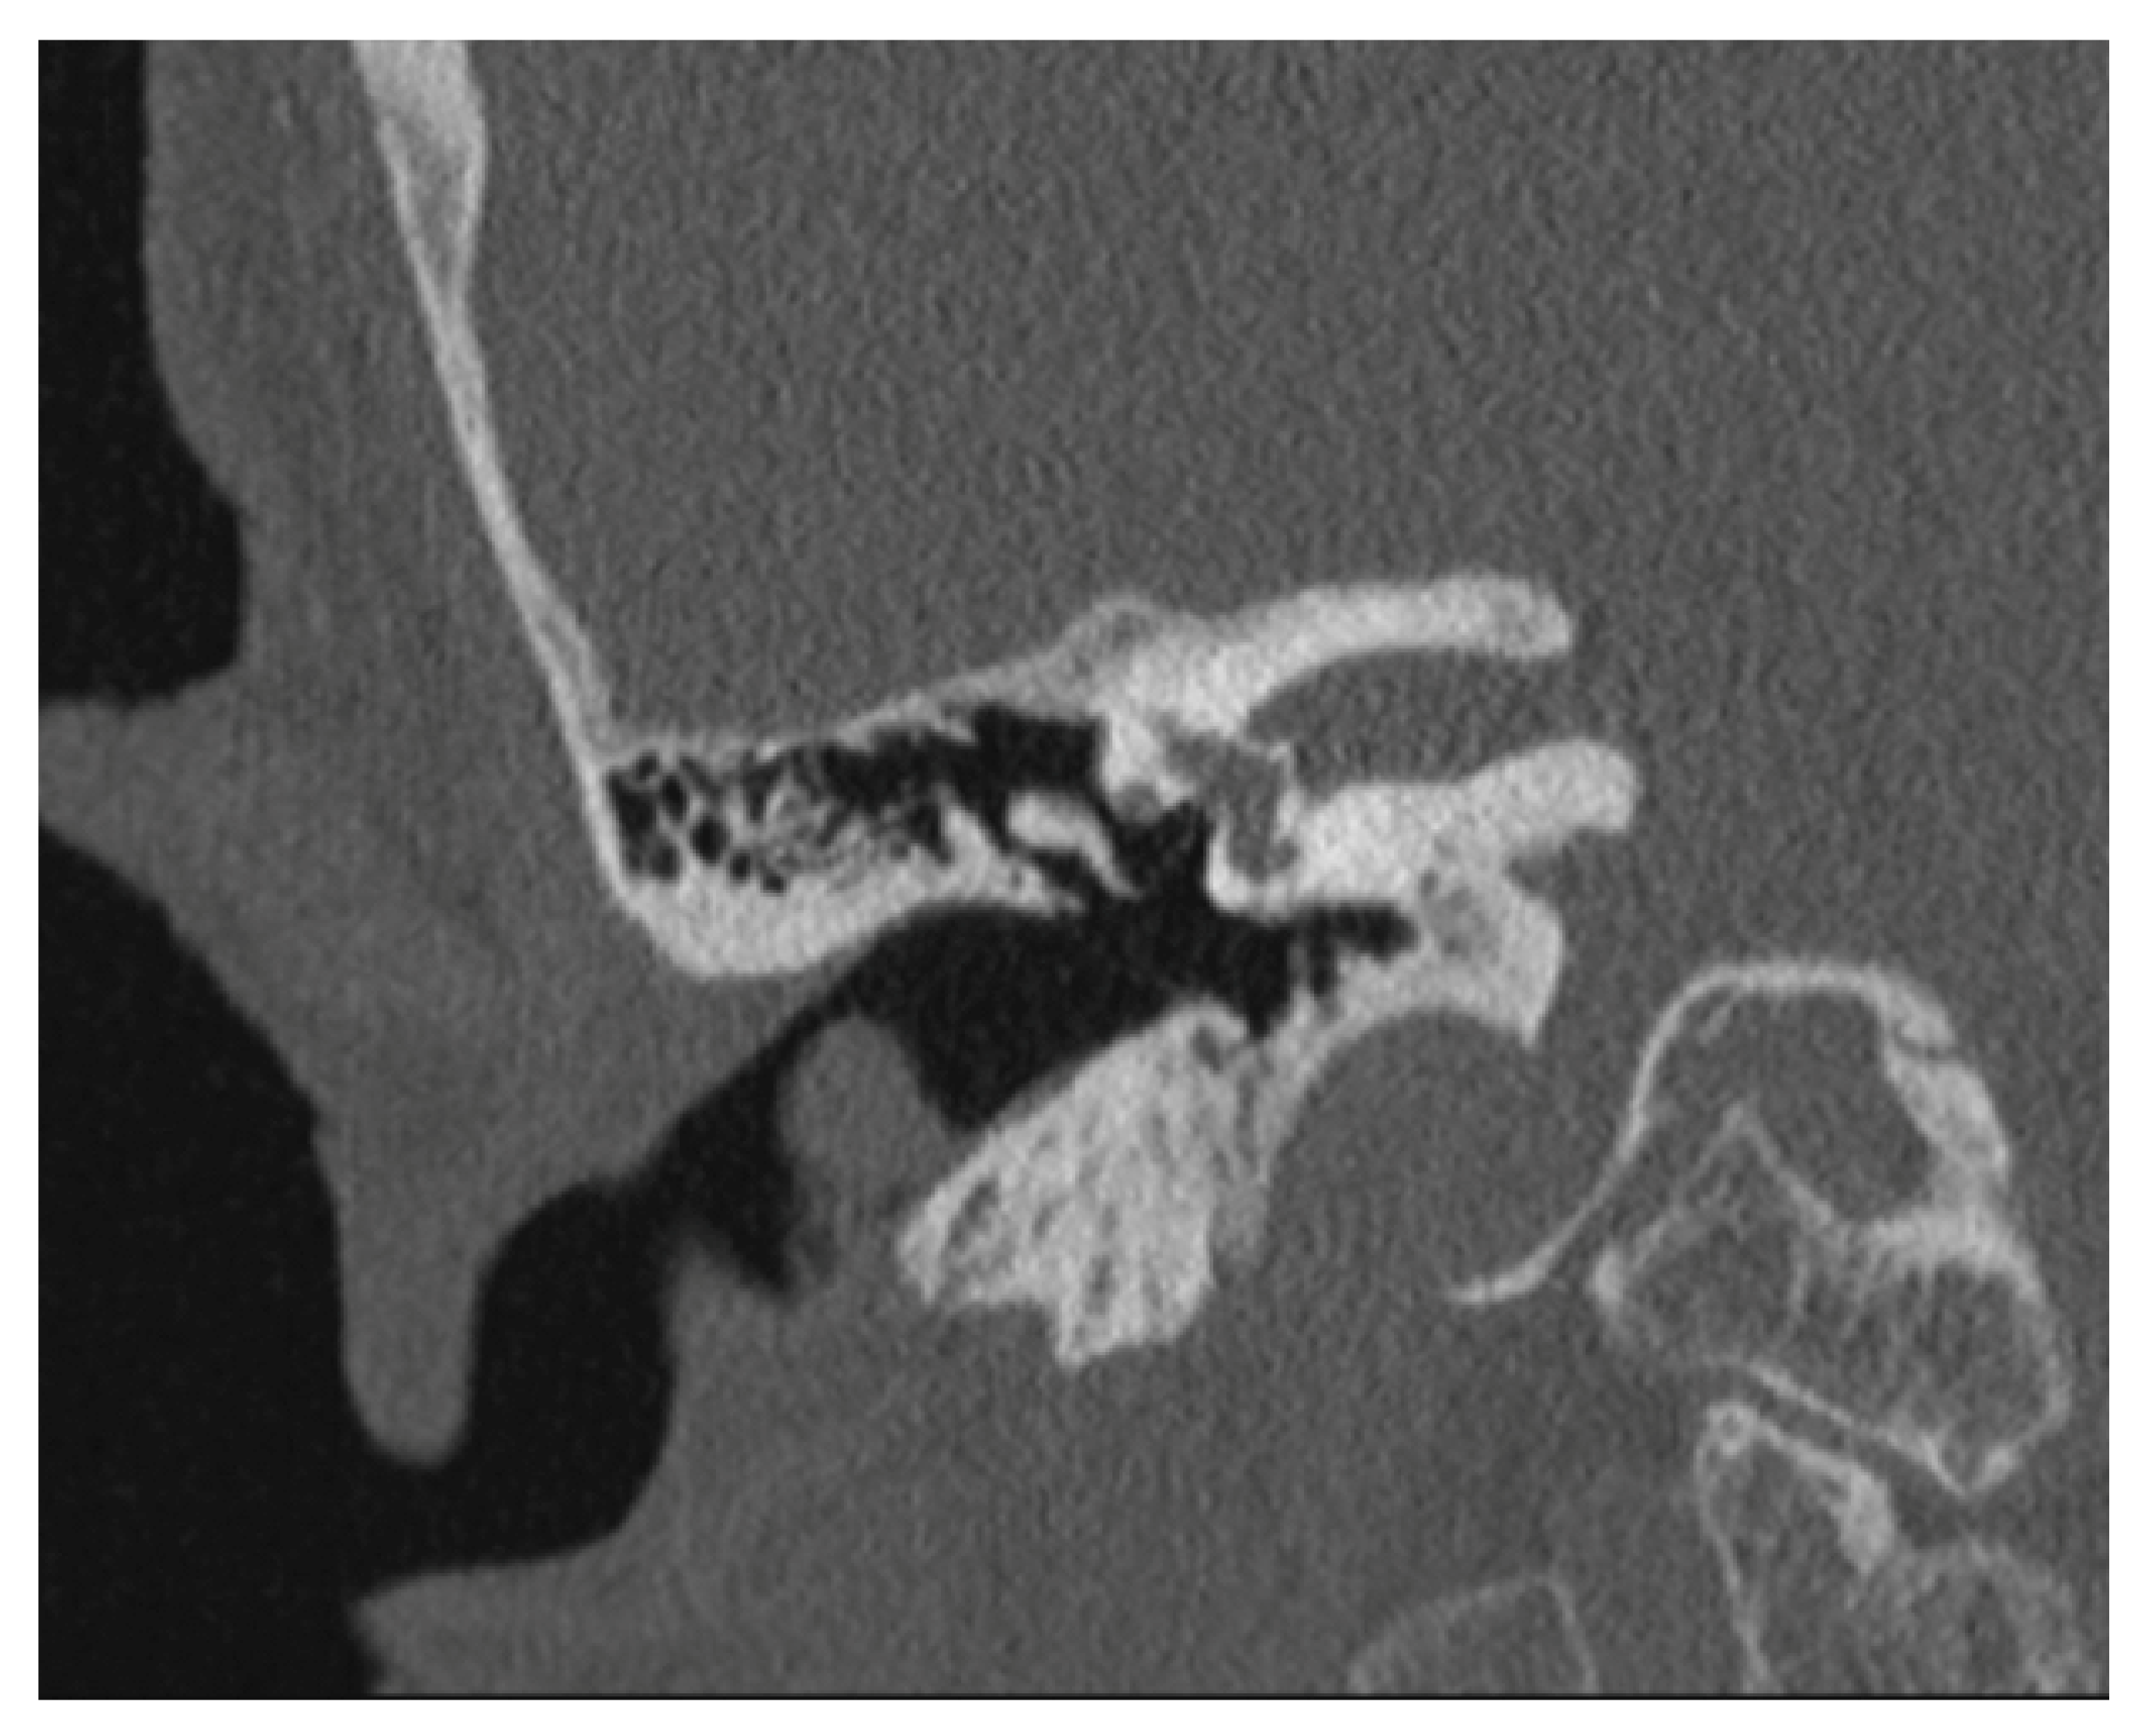

2. Presentation of Case Report

| Our case | 1/87/f | posterior | A | 13 × 10 × 6 mm | End-Exc | No rec |